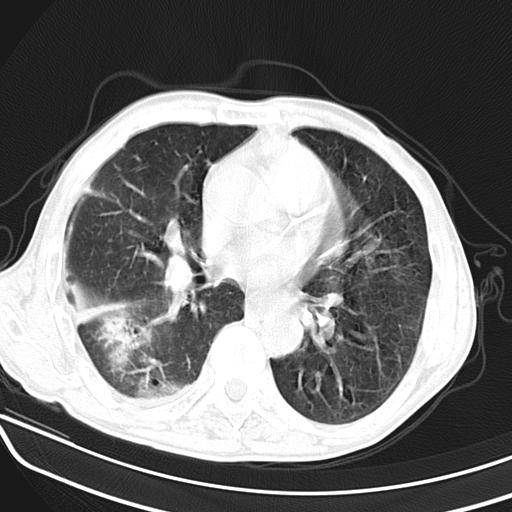

抗炎治疗10天后复查

抗炎治疗10天后复查:右上肺模糊阴影明显减少。